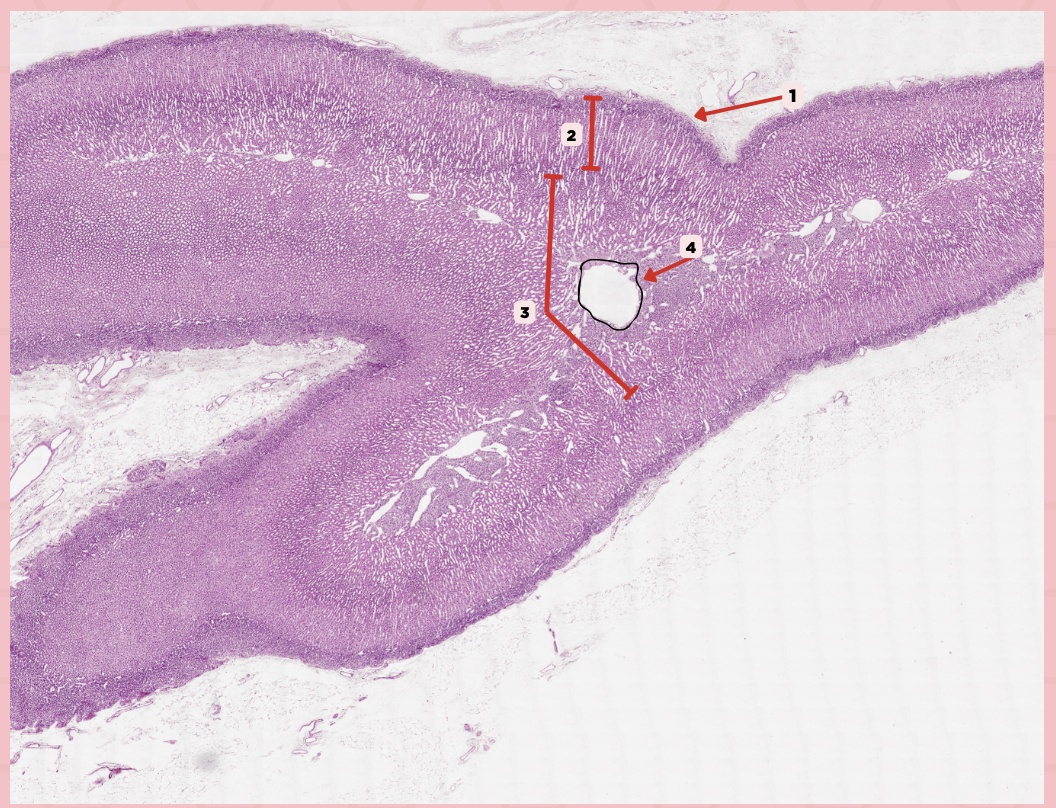

Parathyroid Capsule

Identify the structure labeled as 1.

Lobules

Identify the structure labeled as 2.

Septa

Identify the structure labeled as 3.

Parathyroid

Identify the specimen.